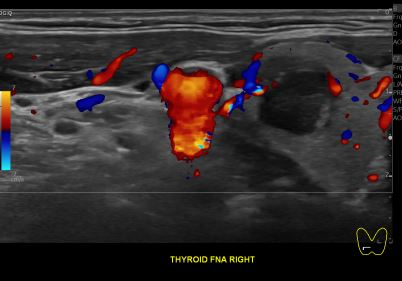

상기환자 외부건진 갑상선 이상소견으로 정밀검사위해 내원하신 40대 후반 여성분으로

의심스러운 갑상선 우엽 세포검사후 갑상선암으로 진단되었습니다